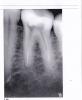

zubiki Опубликовано 5 июля, 2013 Автор Поделиться Опубликовано 5 июля, 2013 Первые два снимка от первоисточника в цифровом формате, только последний с бумаги сканированный. Больше снимков по этому зубу пока нет, будут примерно через месяц, сейчас зуб лечится с лекарством. Но мне хотелось бы сейчас узнать истину, т.к. первый врач продолжает лечение по некоторым другим зубам, и между нами теперь испортились отношения. Он крайне оскорбился, когда я сказала, что подозреваю его в том, что он сломал инструмент в канале. Вторая врач через меня предложила ему посмотреть в канал и обнаружить там инструмент, на что он отказался, сказав, что не собирается искать "мнимый инструмент". В свою очередь первый врач предложил опубликовать мои снимки на форумах и спросить у других врачей, есть ли на снимках сломанный инструмент. Я себя чувствую крайне неловко. Между мной и первым врачом теперь царит атмосфера недоверия, в которой долечивать зубы крайне дискомфортно. Я же чувствую обиду на врача за то, что скрыл от меня, что сломал инструмент (если это так), и оставил канал непройденным (это однозначно, проходили мы его вместе со вторым врачом), успокаивая меня тем, что зуб со временем перестанет болеть сам. Я чувствую себя обманутой. Обидно просто до слез, если это так, потому что я ему доверяла, как себе. Лечила 2 года у него зубы, весь рот перелечила, он лечил всю мою семью, со временем стал чуть ли не членом нашей семьи. После этого случая я ему доверять больше не могу, подозревая в непорядочности. А для меня порядочность врача стоит наравне с профессионализмом. По какой причине канал он не прошел, если там не было инструмента? Почему он в одном корне запломбировал каналы не до верхушек в первый раз? Почему со второй попытки получилось не намного лучше? Подгружаю еще один снимок (не совсем удачный), сделанный после первого пломбирования (цифровой), если он чем то может помочь. Помогите разрешить спор - есть ли инструмент, или его нет. Вторая врач настолько же уверена в том, что инструмент там есть, насколько первый уверен в том, что его там нет. Первый предлагает сделать томографию для проверки, вторая врач с большим старанием пыталась вымыть инструмент из канала, будучи полностью уверенной, что он там есть. Вопрос для всех троих принципиальный. Ссылка на комментарий

Magdalena Опубликовано 6 июля, 2013 Поделиться Опубликовано 6 июля, 2013 (изменено) Сломанного инструмента не вижу. Если инструмент сломан и обойден рядом и канал запломбирован на всю длину - прогноз хороший, сам по себе отломок опасности не представляет.Если зуб у Вас в состоянии как в посте №2, т.е. с недочищенным по стенкам материалом, то отличить оставшийся материал от отломка по КТ проблематично. Изменено 6 июля, 2013 пользователем Magdalena 1 Ссылка на комментарий